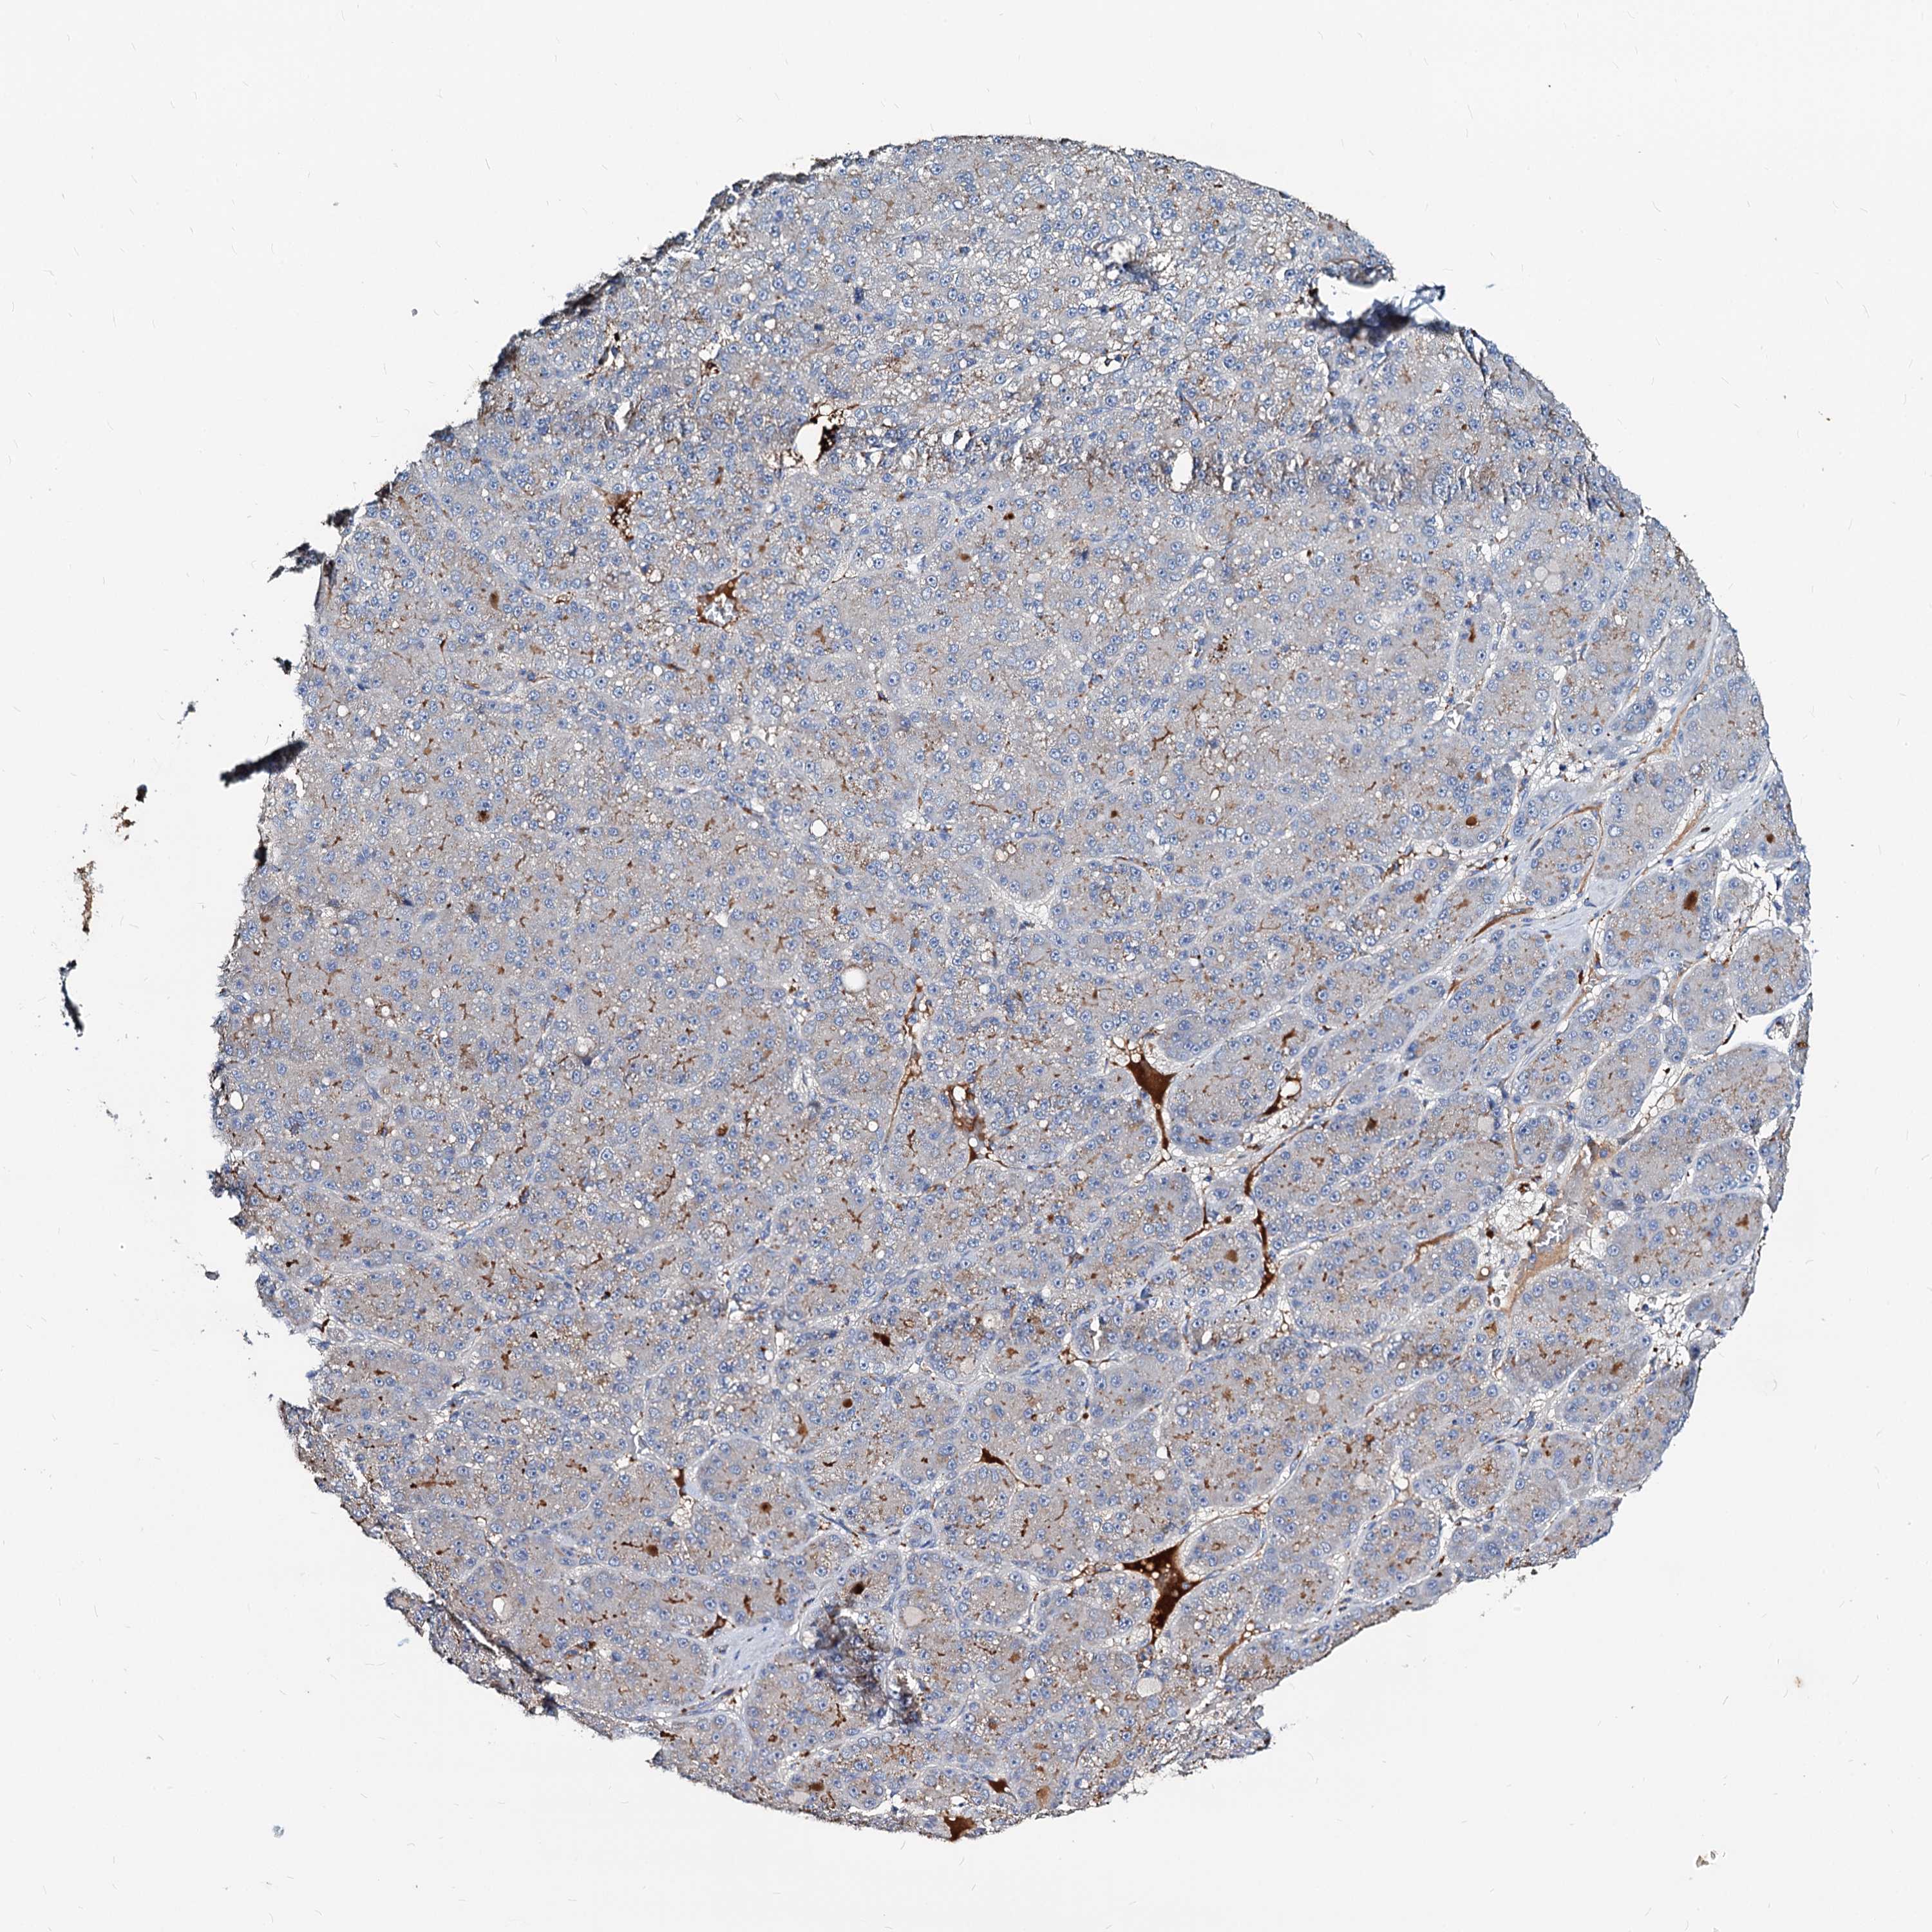

LIVER CANCER - Protein expressioni

A mouse-over function shows sample information and annotation data. Click on an image to view it in a full screen mode. Samples can be filtered based on level of antibody staining by selecting one or several of the following categories: high, medium, low and not detected. The assay and annotation is described here.

Note that samples used for immunohistochemistry by the Human Protein Atlas do not correspond to samples in the TCGA dataset.

Antibody stainingi

Antibody staining in the annotated cell types in the current human tissue is reported as not detected, low, medium, or high, based on conventional immunohistochemistry profiling in selected tissues. This score is based on the combination of the staining intensity and fraction of stained cells.

Each image is clickable and will lead to virtual microscopy that enables deeper exploration of all samples and also displays staining intensity scores, fraction scores and subcellular localization as well as patient and tissue information for each sample.

Antibody HPA039219

Antibody HPA048187

Staining

High

Medium

Low

Not detected

Intensity

Strong

Moderate

Weak

Negative

Quantity

>75%

75%-25%

<25%

None

Location

Nuclear

Cytoplasmic/membranous

Cytoplasmic/membranous,nuclear

Cholangiocarcinoma

Carcinoma, Hepatocellular, NOS